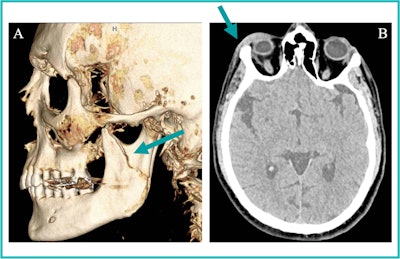

35-year-old transgender woman presents with (A) a 3D CT reformation of the face in the sagittal plane showing a left mandibular fracture (arrow). (B) An axial head CT image from one of three head CT studies over the last two years reveals right periorbital soft tissue swelling (arrow). The radiologist reader suspected intimate partner violence based on radiology reports, which was subsequently confirmed through clinical note examination. Image courtesy of the RSNA.